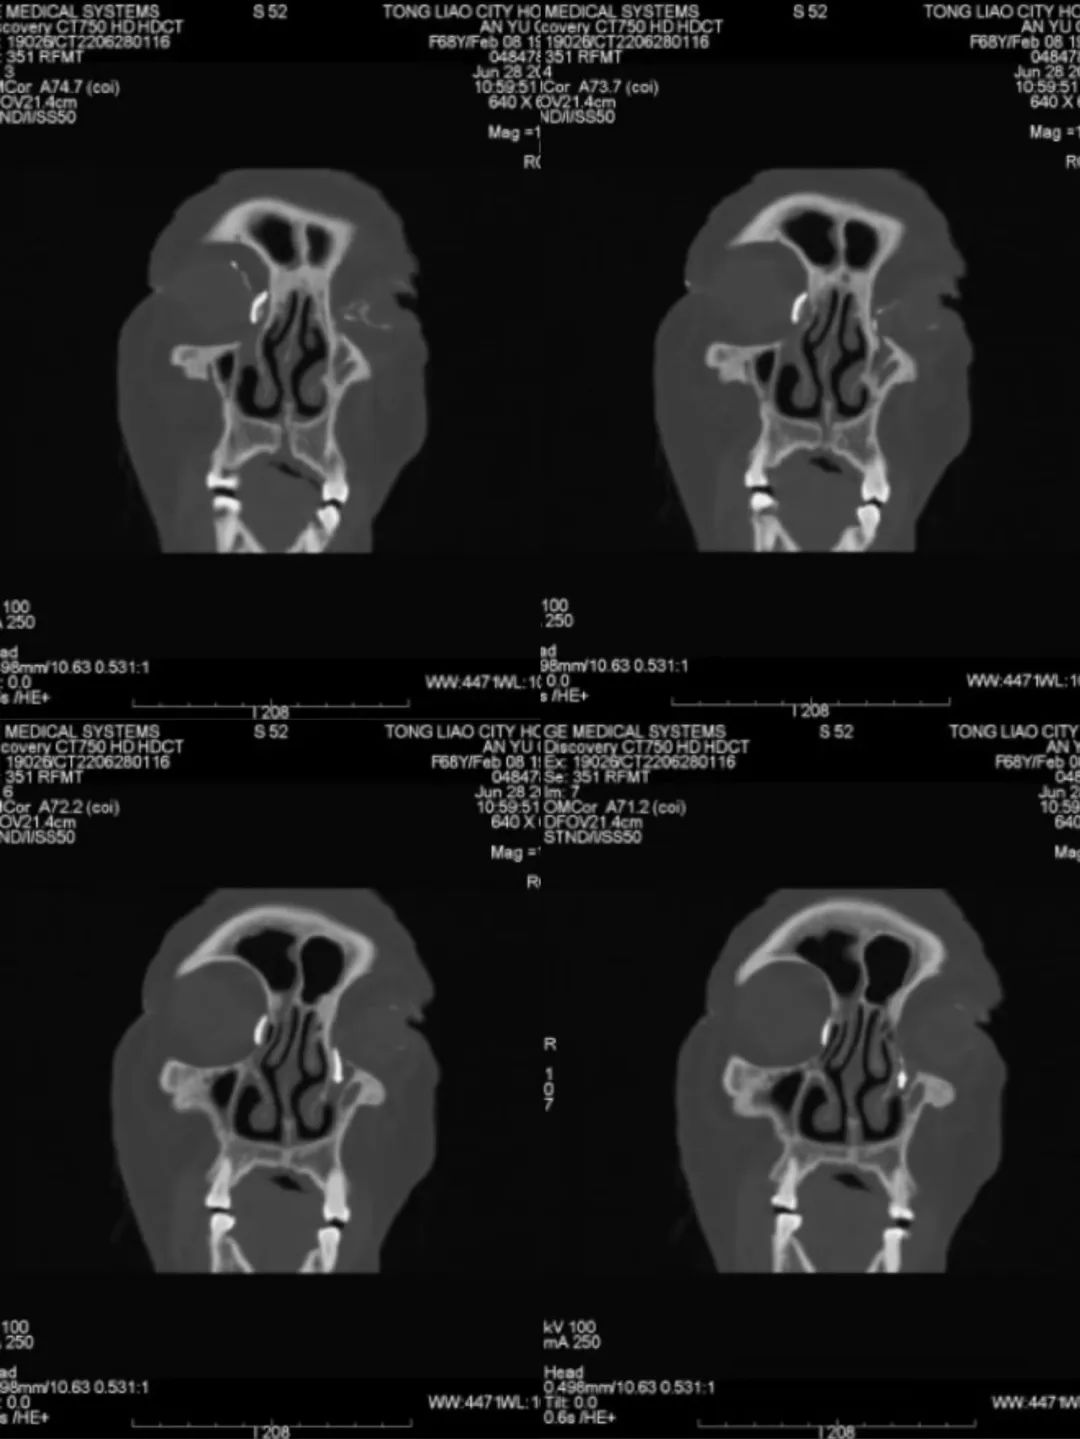

患者女性,68岁,因左眼流泪、流脓于2021年6月在外地行泪小管切开+泪小管息肉切除术,术后8个月患者左眼再次出现流泪、流脓症状,同时右眼也出现流泪伴分泌物增多症状,于我院眼科就诊。张广良副主任医师经过详细询问病史,仔细查体,给予患者行泪道造影检查后,请许莉主任医师会诊,最终确诊为“右眼慢性泪囊炎,左眼泪道阻塞”,完善术前检查,排除手术禁忌症后,由张广良医生给予患者在全麻下行内窥镜下泪囊鼻腔吻合+泪总管息肉切除+人工泪道插管植入术,术后泪道冲洗通畅,患者流泪、流脓症状消失。术后和术前对比,外观看不出来做过手术,体现出了微创的外科手术理念。

鼻内窥镜下泪囊鼻腔吻合术是目前国内治疗慢性泪囊炎、泪道肿瘤等泪道相关疾病最为先进的手术方式,具有微创、手术时间短、出血少、成功率高、颜面部皮肤无瘢痕、患者满意度高等特点,正在逐渐取代大部分传统外部手术,逐渐应用于临床,服务于广大泪道疾病患者。